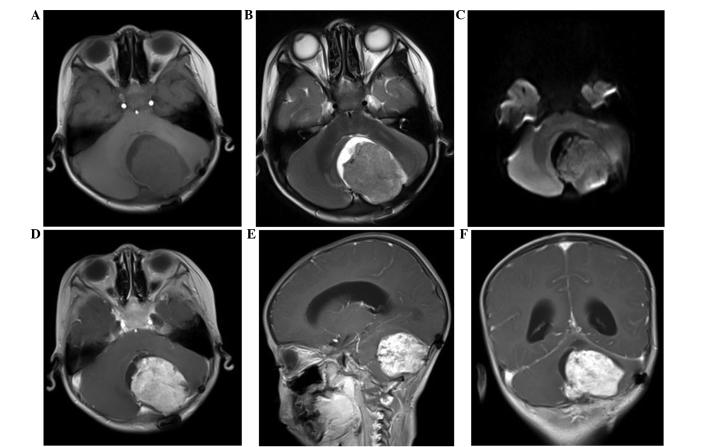

Endodermal sinus tumors are rare malignant germ cell tumors that usually originate from the gonads and are rarely observed extragonadally. Pure primary endodermal sinus tumors of the cerebellar hemisphere are extremely rare and patients diagnosed with the disease often have a poor prognosis. The symptoms of YSTs are unspecific and associated with the location of tumors. Intracranial YSTs (such as cerebellar hemispheres) always present with symptoms including headache and poor vision. The present study reports the case of a three-year-old male who presented to The First Affiliated Hospital of Nanchang University (Nanchang, China) with a headache that had persisted for one month, and then worsened for the last 10 days. This was accompanied by vomiting and gait disturbance. An abnormal signal mass was identified in the left cerebellar hemisphere on brain magnetic resonance imaging. The case initially presented as a medulloblastoma and the patient was followed up for six months. The final pathology report revealed an endodermal sinus tumor, also known as a yolk sac tumor. Six months following resection of the left cerebellar tumor, the patient succumbed to recurrence of the disease, due to acute vomiting and severe headache.